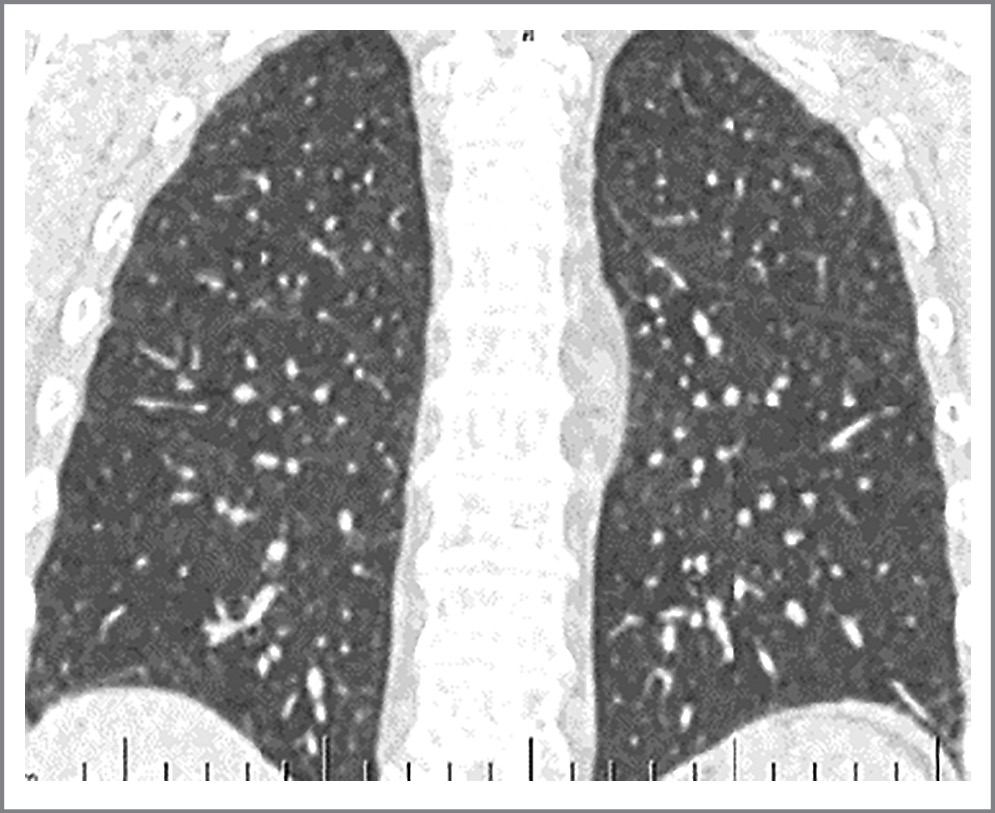

В позднем послеоперационном периоде (месяц после операции) признаки пневмонии по данным КТ органов грудной клетки полностью регрессировали. Антител к SARS-CoV-2 у пациента не выявлено (рис. 7).

Рис. 7. КТ легких через месяц после операции, фронтальная проекция.